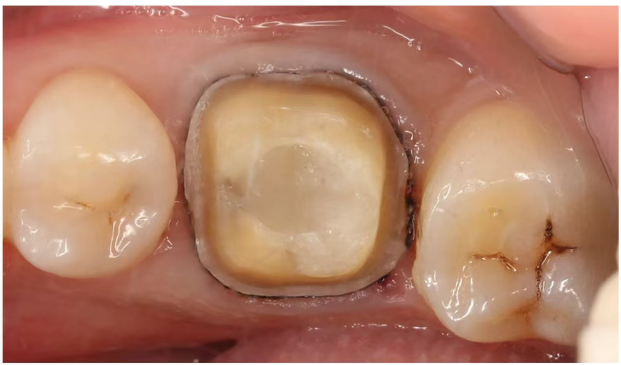

第四次就诊

观察一月无症状后,上障,

涡轮机去除封药后,全酸蚀,涂布3M第八代粘接剂,

F00+LS内部重建,牙体预备,制作全瓷冠。

第五次就诊

去除暂冠,清洁基牙,隔湿,玻璃离子粘接。

4个月复查

戴牙四月复查,可见修复体及牙周情况良好,

正常行使功能,日常使用无异常。

8个月复查

治疗术后八月复查,糊剂固化稳定,

根分叉处及牙周膜影像较术后两月有明显改变。